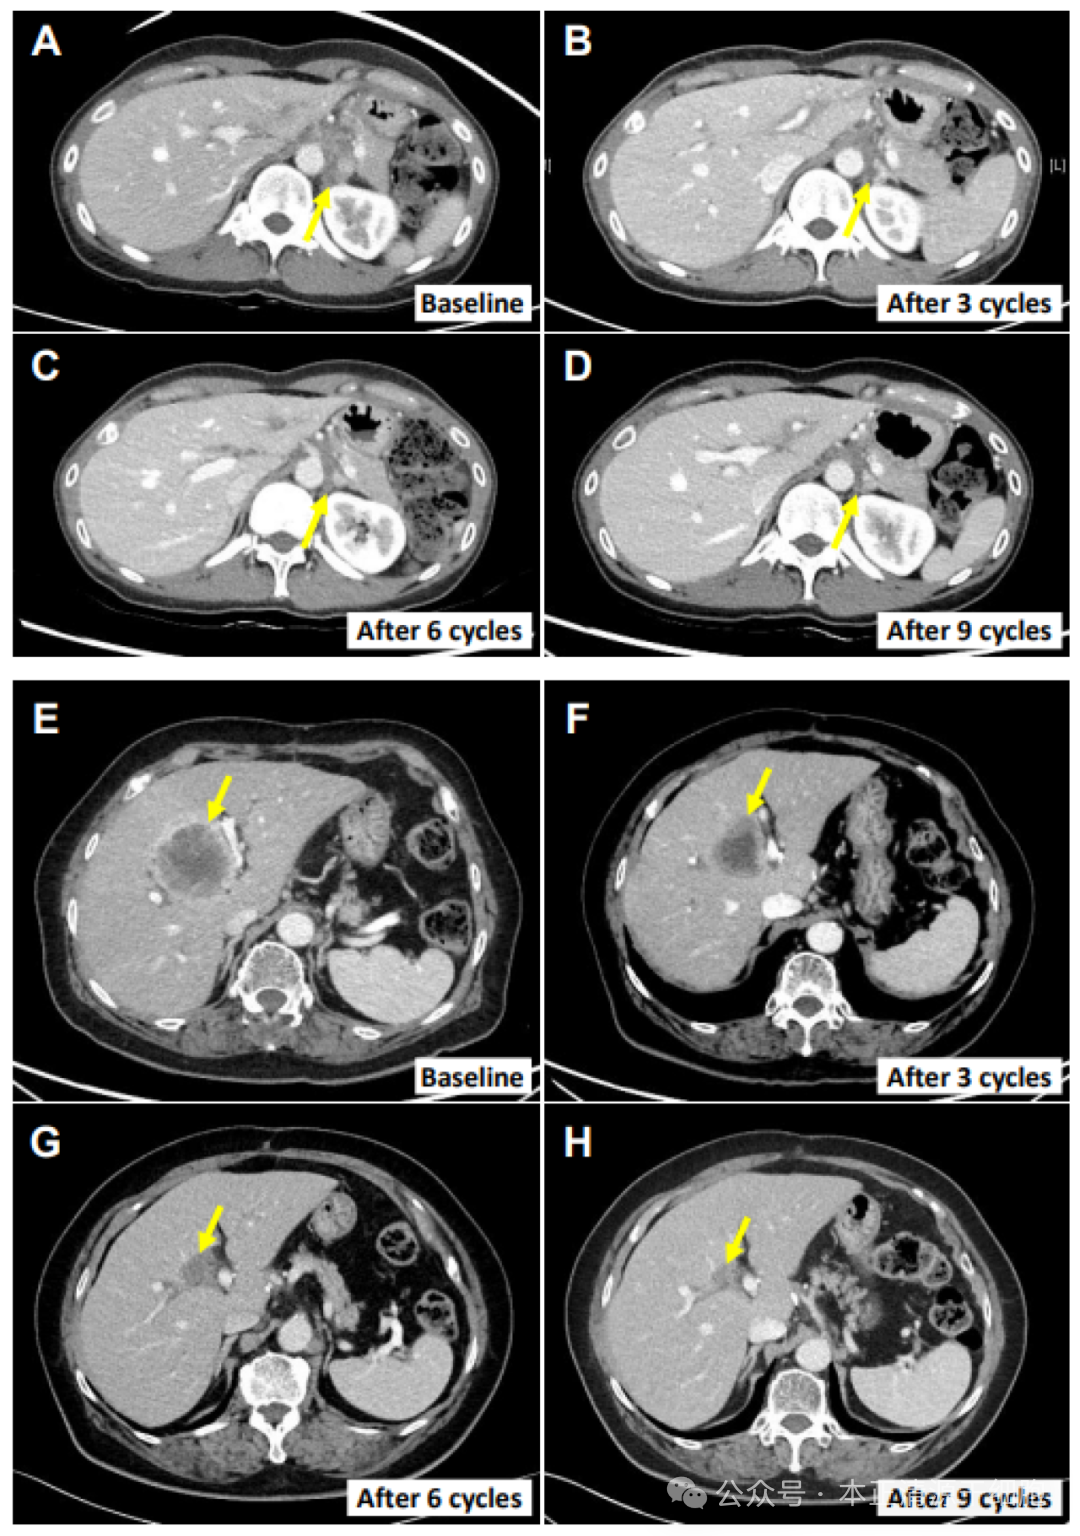

NK(自然杀伤)细胞作为人体免疫系统的核心防御单元,其主要职能在于高效识别并清除入侵的病原微生物与内源性恶性肿瘤细胞,因此被誉为“抗癌第一道防线”。大量科学研究证据表明,NK细胞具备广谱的抗癌活性,这类细胞凭借其独特的“直接效应机制”、“高度敏感性”以及“高反应速率”,不仅对一系列常见恶性肿瘤如肝癌、肺癌、胆道癌、乳腺癌及食管癌等显示出显著的杀伤效果,而且对于诸多其他类型的癌种同样具有潜在的抑制与清除能力。韩国首尔延世大学医学院的临床研究人员在行业期刊《Cancers (Basel)》发表了题为Safety and Efficacy of Allogeneic Natural Killer Cells in Combination with Pembrolizumab in Patients with Chemotherapy-Refractory Biliary Tract Cancer: A Multicenter Open-Label Phase 1/2a Trial的研究成果。这项关于自然杀伤细胞(NK cell)与PD-1抑制剂联用治疗晚期胆道癌的研究报告,揭示了相较于单一疗法,NK细胞与PD-1抑制剂的联合治疗策略在改善临床疗效方面展现出显著优势。该研究旨在探索NK细胞与帕博利珠单抗联合疗法对化疗难治性胆道癌的治疗潜力。研究共招募56例患者,其中,6例符合标准的患者进入1期试验,而34例符合标准的患者及1例源自1a期试验的患者被纳入2a期试验阶段。在治疗周期的首两周内,患者接受了高活性的同种异体自然杀伤细胞,同时于第一周同步接受帕博利珠单抗疗法。此后,遵循此三周为一疗程的规律,对患者进行周期性的治疗重复。经过三个周期治疗后的肿瘤反应评估显示:在第一阶段,六名患者中的四名(66.7%)共经历七次不良事件,但无严重不良事件报告。进入第二a期,29名受试者(占85.3%)累计出现126起不良事件。整体来看,总缓解率(ORR)为17.4%,而各治疗方案的ORR均值则达到50.0%。 图:两名患者的癌症消退值得注意的是,患者E0107为一例40岁女性,因胆囊炎行胆囊切除术,术后病理确诊为胆囊癌合并腹膜癌。其病史中已包含使用吉西他滨、顺铂、5-氟尿嘧啶(5-FU)、伊立替康脂质体及亚叶酸等多种化疗药物的治疗经历。在采用NK细胞疗法联合帕博利珠单抗治疗后,其转移性淋巴结体积显著缩小,减小幅度高达82.3%。不少癌症患者面对晚期、疾病复发、病灶扩散等严峻挑战时,迫切寻求具有更高临床效益的治疗方案。经过大量的临床研究,已证实NK(自然杀伤)细胞在对抗肝癌、肺癌等常见实体瘤中的关键作用。NK细胞凭借其高效的肿瘤杀伤效果、广泛的应用范围以及在处理晚期、复发、转移等复杂病情时的独特优势,为癌症患者提供了极具前景的治疗选项。